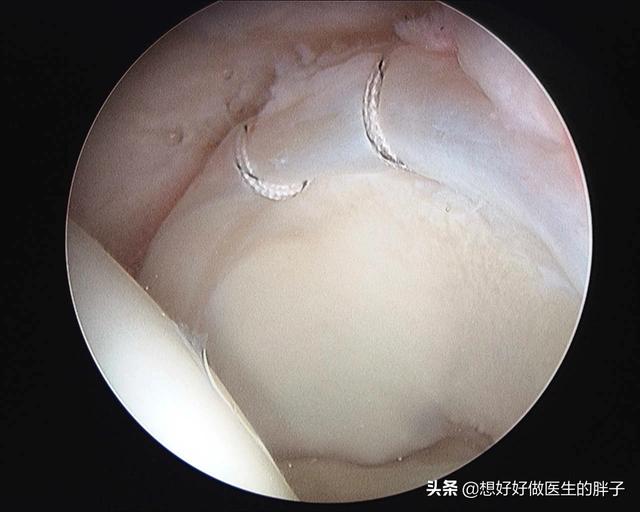

●如果核磁显示髋臼盂唇撕裂的比较严重,那么可能要进行髋关节镜下的盂唇缝合手术,同时要在关节镜下将撞击的因素比如增生的骨赘去除掉,下图就是已经撕裂盂唇缝合以后的影像学资料,这样恢复了盂唇的稳定性,去除了导致撞击的因素,以后经过系统的康复锻炼与恢复,慢慢症状就会消失了。